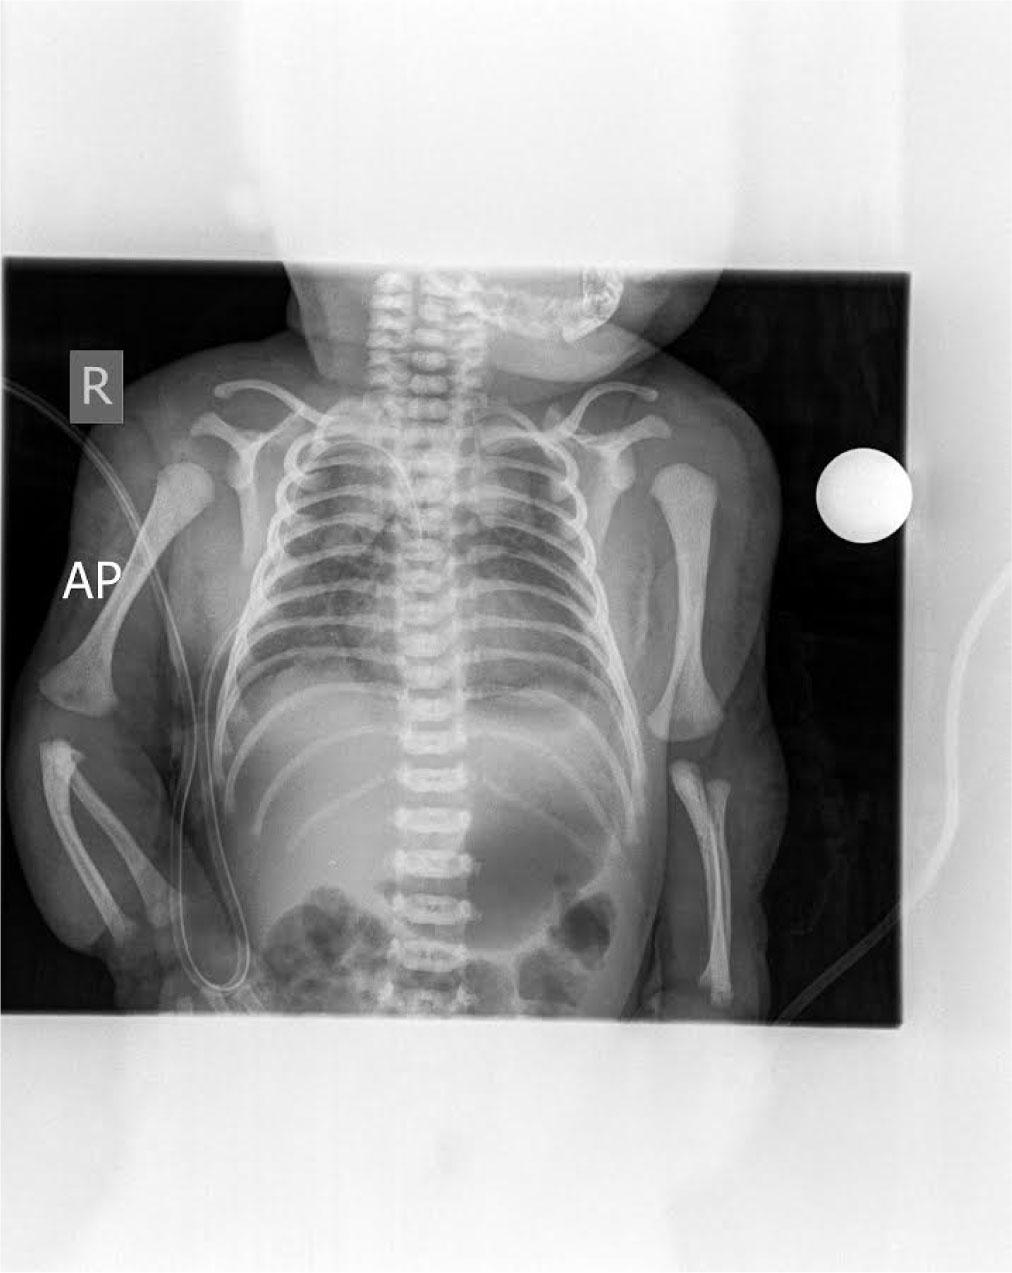

“Halo” sign of pneumopericardium on chest radiograph

A term male infant, weighing 2700 grams at birth, was born at 39 weeks to a healthy mother (blood type O, Rh positive) delivered spontaneously by vaginal route. Pregnancy was well monitored and unremarkable. The infant cried immediately after birth and did not require any interventions. He had a birth weight of 2700 grams, a length of 52 cm and a head circumference of 34 cm. Apgar scores were 9 and 9 at 1th and 5th minutes, and infant was transferred to the postnatal unit with his mother for regular postnatal care. During the third hour of age, his skin started to become diffusely livid with evidence of respiratory distress, tachypnea (respiratory rate = 63/min) and heart rate 136/min. He was transferred to the neonatal intensive care unit (NICU) for investigation and further management. On admission, his vital signs showed a temperature of 36.6 °C, heart rate of 101 per minute and respiratory rate of 68 per minute. His blood pressure was 77/50 mmHg and his weight reduced to 2680 grams. Capillary blood gas analyzed on a Gem Premier 3000 gas analyzer showed pH 7.05; PaCO2 13.1 kPa; PaO2 2,4 kPa; bicarbonate 27.1 mmol/l; base excess of −3,4 and SaO2 84%. Nasogastric tube was placed. The chest examination showed chest retraction as compared with abdominal retraction during inhalation – 2 points; retraction of the lower intercostal muscles – 1 point; xiphoid retraction – 0 points; flaring of the nares with inhalation – 1 point; grunting on exhalation – 1 point, suggesting Silverman score = 5 points which indicates moderate respiratory distress. In view of his respiratory distress, the infant remained in the incubator and hood with 40% fraction of inspired oxygen (FiO2) was applied and 20 mg of Theophylline (Aminophylline®) given 5mg/12hours. A chest radiograph revealed bilateral apical pneumothorax in Figure 1. A chest drain was placed between anterior and midaxillary line in the 5th right intercostal space. The procedure was done in aseptic conditions after the area was cleaned with 0.015% chlorhexidine and spontaneously dried for half a minute. A dose of 0.3ml/kg of 1% lignocaine was subcutaneously applied. An incision was made using a sterile scalpel above the inferior rib. An incision place was carefully pinpointed to avoid a well-known location of important neurovascular structures right below the superior rib. The chest drain was fixated using two sterile surgical stripes. The secondary capillary blood gas analysis showed pH 7.10; PaCO2 10.4 kPa; PaO2 3,4 kPa; bicarbonate 24.2 mmol/l; base excess of −5,5 and SaO2 was 89%. The following day radiological signs of bilateral partial pneumothorax showed mild signs of resolution. Blood gas analysis on showed pH 7.35; PaCO2 5.5 kPa; PaO2 3,8 kPa; bicarbonate 22.6 mmol/l; base excess of −3 and SaO2 was 94%. The next morning the infant had tachypnea and dyspnea with SaO2 89%. Cardiovascular examination showed muffled heart sounds with no audible murmur and heart rate 123 per minute. Chest X-ray showed complete resolution of pneumothorax however classical ‘Halo’ sign appeared, (a collection of air surrounding the heart in the pericardial sac) indicating existence of pneumopericardium, which can be seen in Figure 2. The infant became acidotic and SaO2 dropped to 83%. Due to inadequate fixation of the chest drain, it spontaneously moved and may have damaged the pericardial sac. Along with the already existing pneumothorax, probably a combination of ventilation mechanism and trauma resulted in air leak into the pericardial sac. The chest drain was therefore repositioned (extracted by 3 centimeters) and due to possible progression to life threatening cardiac tamponade the infant had to be closely observed with cardiorespiratory monitoring and series of chest radiographs. Over the course of next 24 hours the clinical and radiographical signs of pneumopericardium resolved. Respiratory rate was 42 per minute and heart rate was 115 per minute. SaO2 was 96%. Thoracal drain was then removed and latter subsequent chest radiographs showed no recurrence of either pneumothorax or pneumopericardium (Figure 3). The infant remained in incubator under diffuse oxygen therapy with FiO2 40% and in the following 48 hours his oxygen requirement was weaned gradually to room air and was discontinued the next day. He was discharged on 8th day of his life. His regular follow-ups showed he was thriving well.